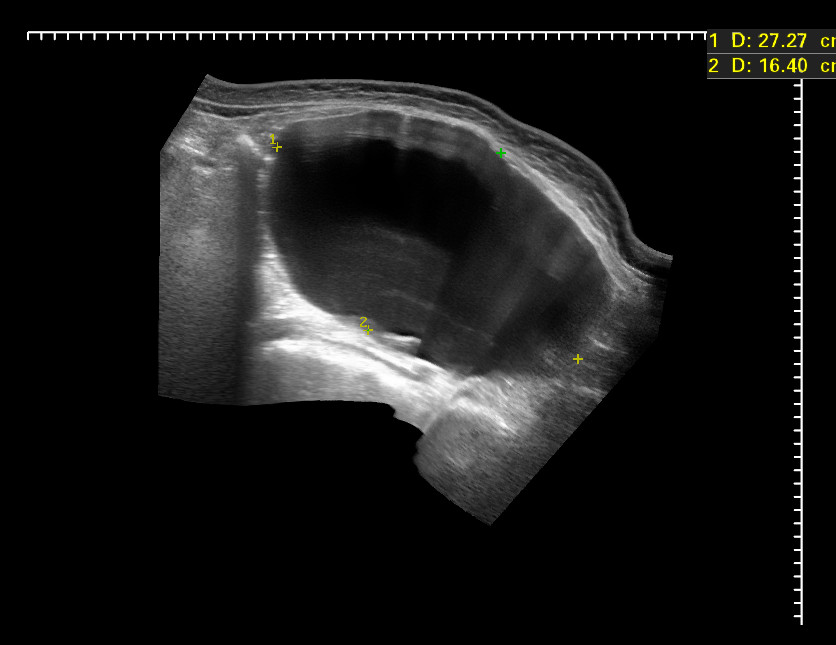

Женщина средних лет с нерезкими болями в животе и его увеличением направлена к гинекологу с подозрением на беременность. Гинеколог отправил на УЗИ исключить кишечную непроходимость.

dec302015130951_0.jpg

dec302015131302_4.jpg

Экстренно отправлена в гинекологическое отделение, где прооперирована.

Д-з: Гигантская киста яичника.

Объем кисты - около 12 литров!

Кстати, если посчитать объем по полученным на УЗИ данным, то получится около 6 литров.

Видимо, измерение по панорамной реконструкции не всегда корректно.